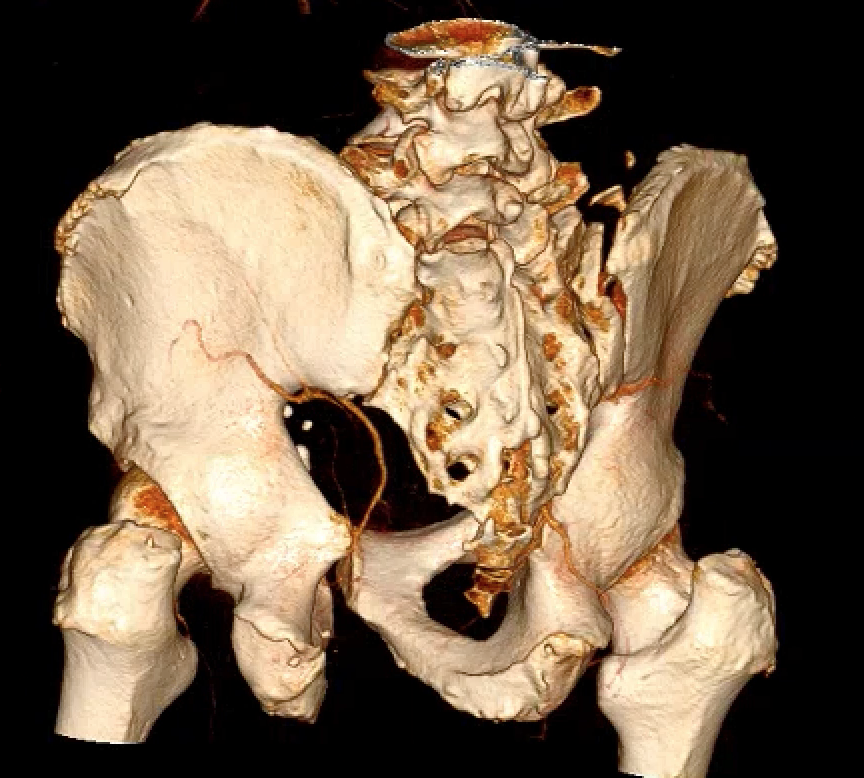

LC-2: Pelvic wing fracture with pubic rami fracture

Crescent fracture variant

Iliac wing fracture that extends into sacrum and associated with SI joint dislocation

Crescent fracture

Operative management

Options

Posterior fixation - iliac plates

Iliac fracture plating

Technique

- use lateral window of ilioinguinal approach